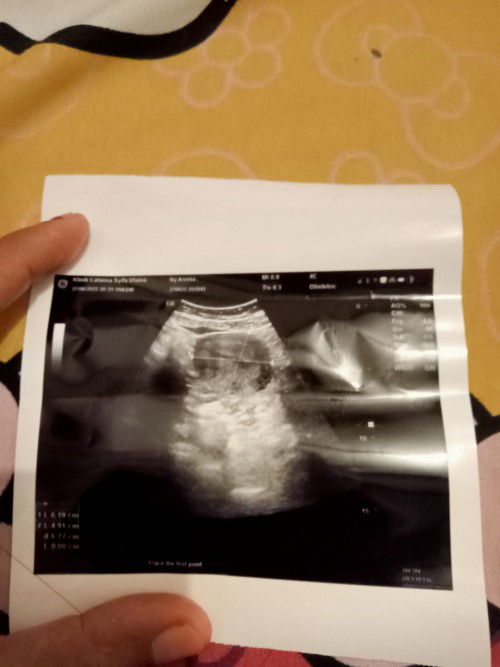

Saya kemarin USG di puskesmas Bun . Alhamdulillah hasilnya baik semua niat mau kontrol letak plasenta Alhamdulillah plasenta di atas . Karena selam 20 Minggu saya sering flek atau darah segar dan sekarang Alhamdulillah sudah membaik. Tidak di sengaja posisi janin sedang bagus nungging gitu jadi kelihatan JK 🥰 prediksi laki laki Bun anak pertama ku perempuan. Jika tidak meleset prediksi USG Alhamdulillah sejodo. #berbagi kebahagian Bun karena awal sempet wori karena seringnya flek saya takut Previa ternyata tidak. 😇😇